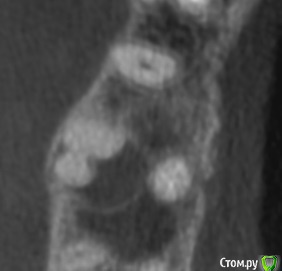

vse32 Опубликовано 8 ноября, 2019 Поделиться Опубликовано 8 ноября, 2019 16 зуб.Тему немного обсудили с хирургами на счет правильной имплантации. Появилось мнение, что реально добиться хорошего результата только эндодонтией. Я имею сомнения на этот счет. Вернее, 50 на 50.Что бы Вы выбрали? Эндодонтическое лечение или сразу имплантация. Ссылка на комментарий

annda Опубликовано 11 ноября, 2019 Поделиться Опубликовано 11 ноября, 2019 Отличный кейс для апикалки щечных корней. Купол кисты - это фактически синус лифтинг, там ведь тоненькая косточка. Если суметь это сохранить и за счет апикалки вырастить там кость, то даже в будущем будет профит немалый 1 Ссылка на комментарий